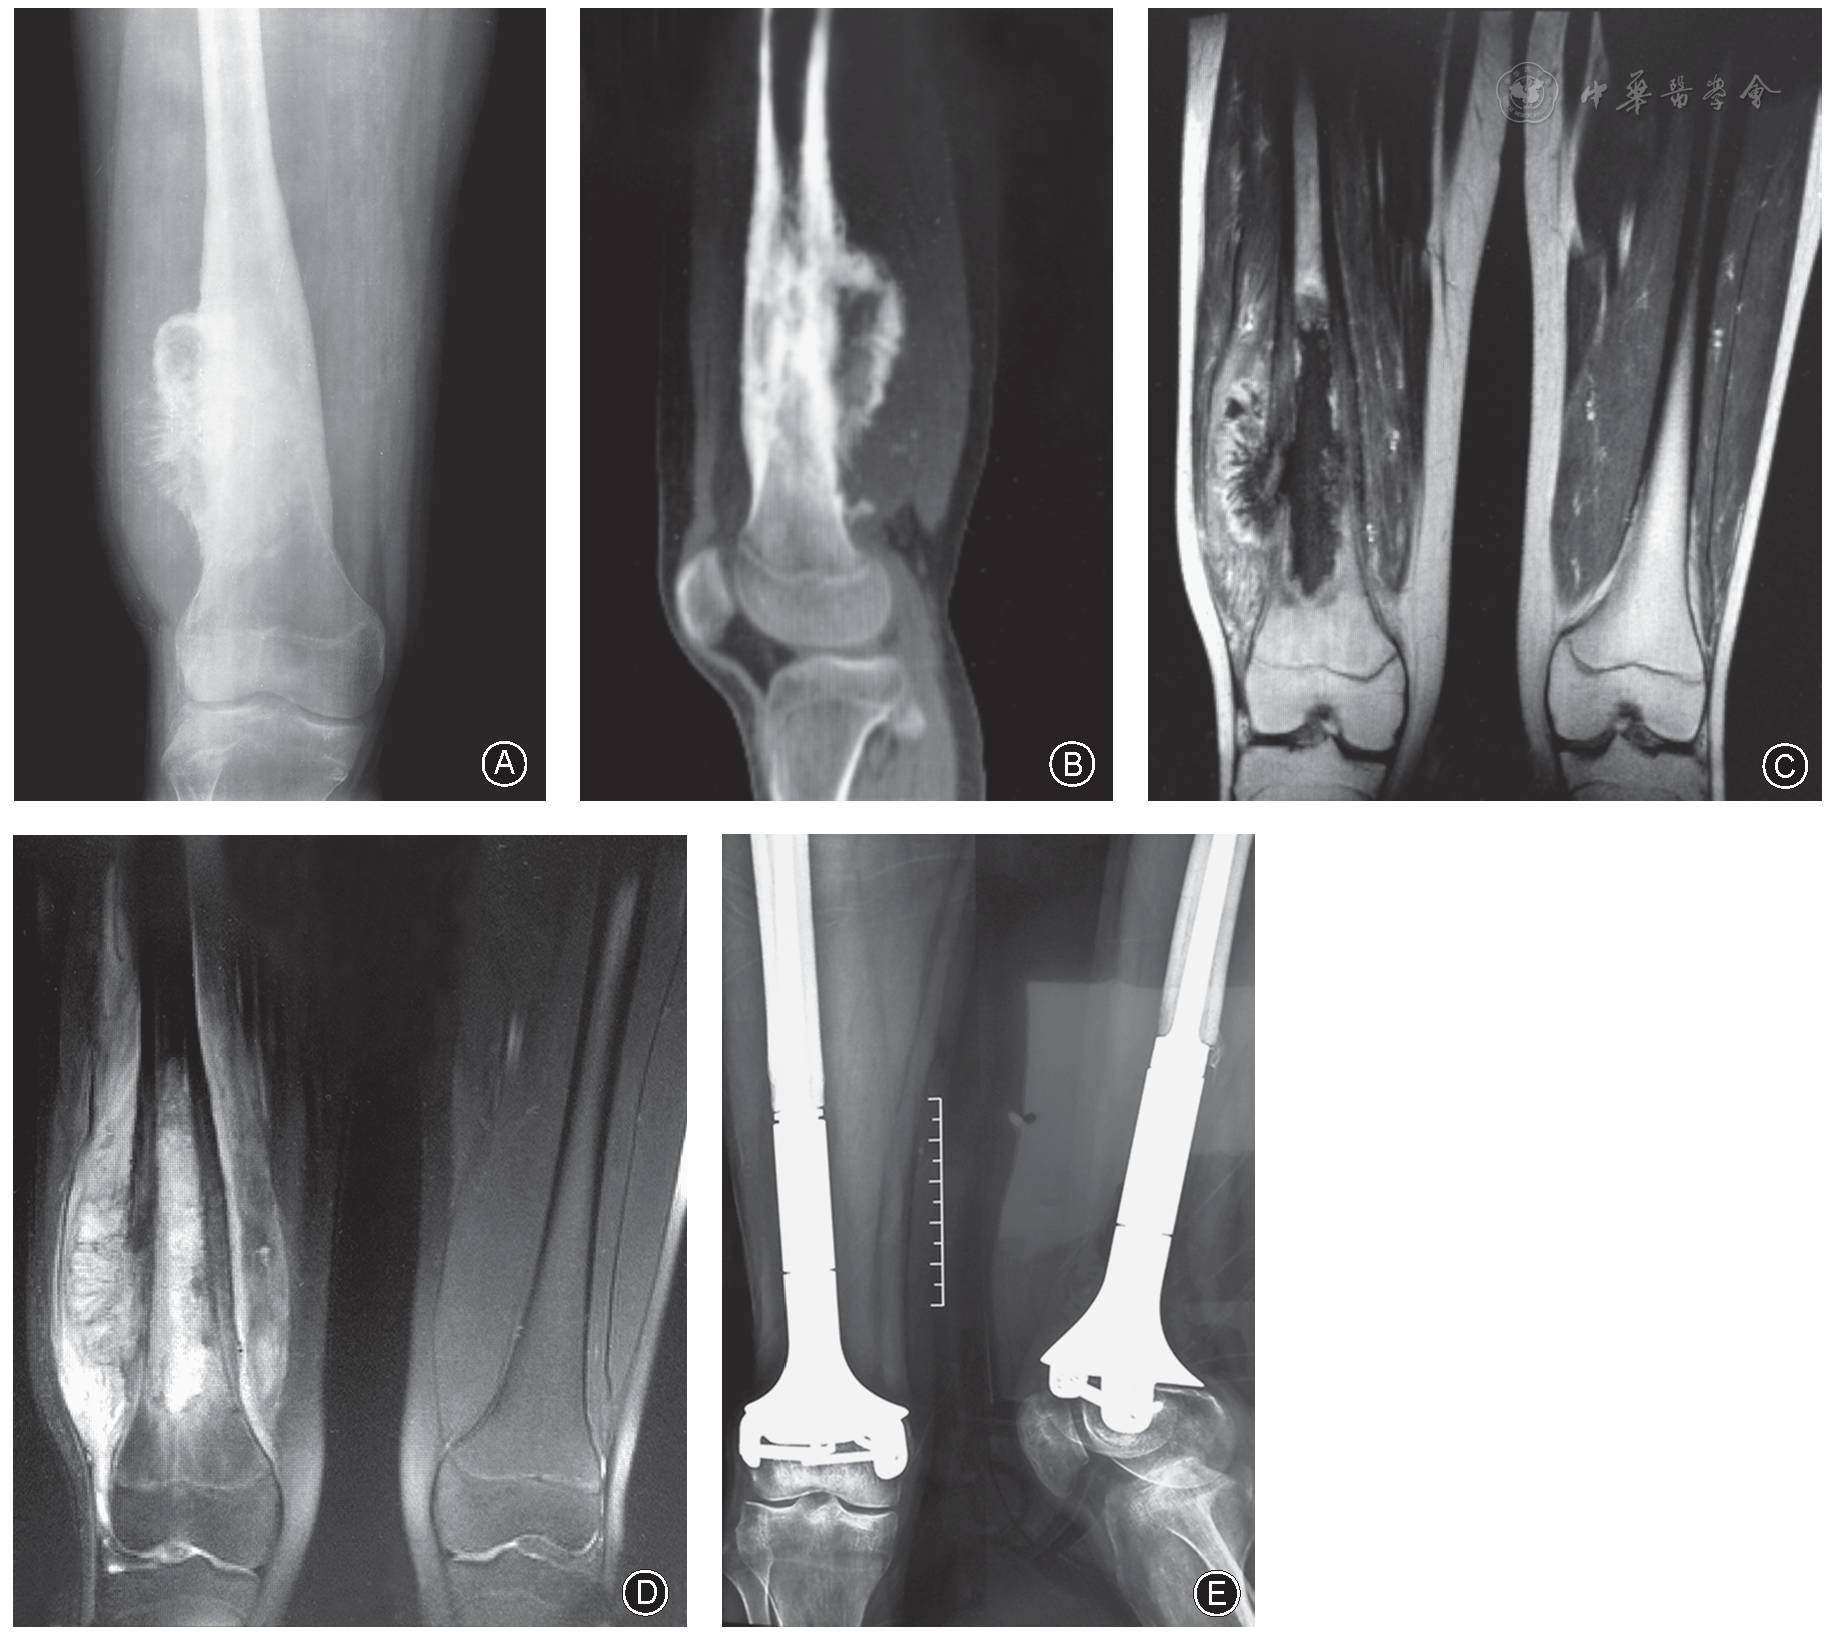

【精彩文章推荐】儿童股骨远端骨肉瘤保留骨骺的定制肿瘤型假体重建术

股骨远端骨肉瘤